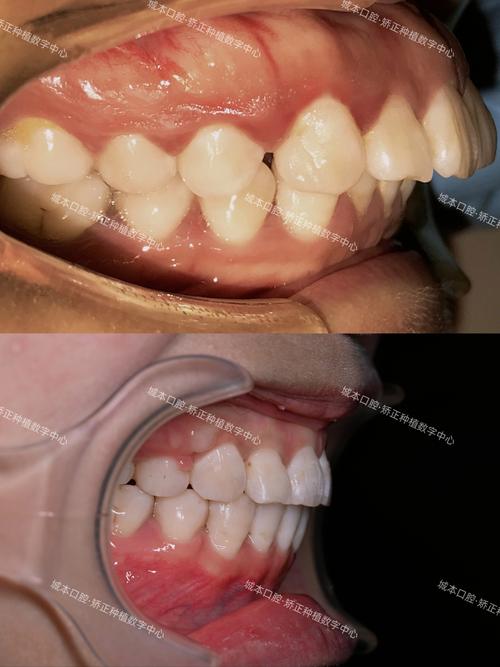

- 纠正后牙反颌/锁颌:改善单侧或双侧后牙反颌(“地包天”的一种类型)及锁颌(牙齿交错无法正常咬合),恢复咀嚼功能,避免颞下颌关节损伤。

- 后牙反颌或锁颌(导致咀嚼功能异常或面部不对称);